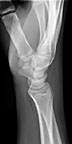

Lateral view |

Views of the wrist